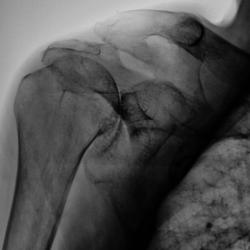

Валентин Львович! Думаю, что имела место травма в виде перелома ключицы и разрыва ключично-акромиального сочленения. Перелом ключицы консолидировался. А разрыв остался с образованием нового сустава (подвижного). Посттравматический артроз плечевого сустава.

Но ведь это можно считать как подвывих?